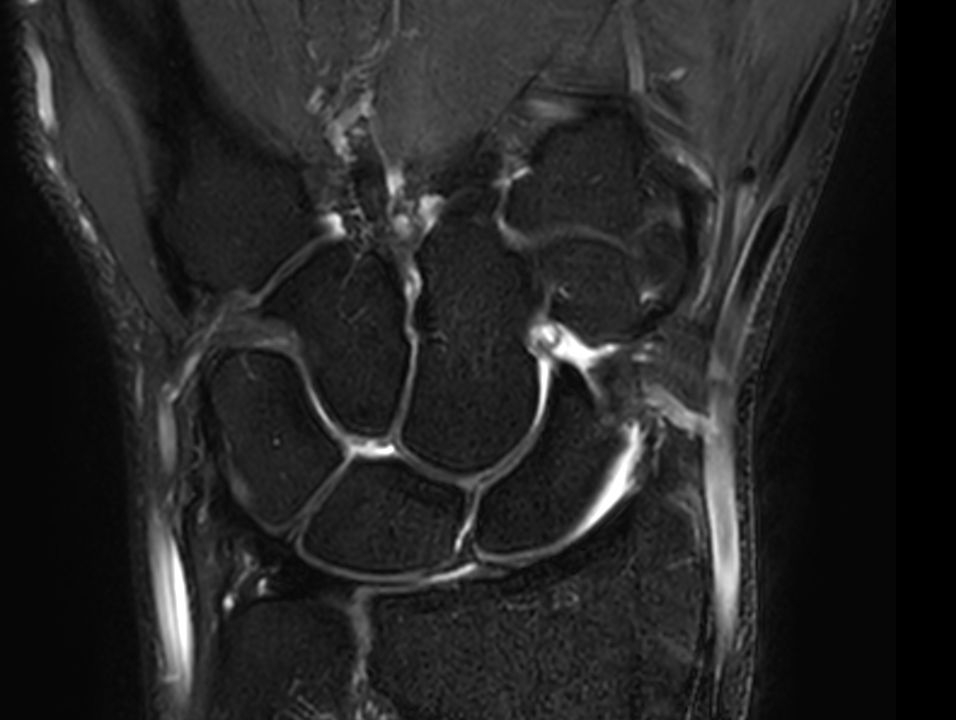

Coronal T2w TSE FatSat

Coronal T2w TSE FatSatSmartSpeed

Coronal T2w TSE FatSatSmartSpeed Resolution